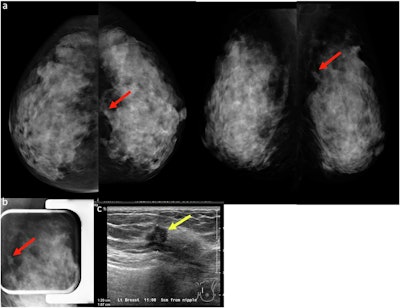

(a) A 45-year-old woman underwent a baseline screening mammogram, which was interpreted as normal by one reader. A second reader identified a possible isodense mass in the upper inner quadrant of the left breast, projected over the retromammary fat (red arrows, left craniocaudal and mediolateral oblique mammograms). (b) Spot compression left lateral-medial mammogram demonstrated an irregular mass with spiculated margins (red arrow) in the area of concern. (c) Targeted ultrasound demonstrated a correlating irregular hypoechoic mass with indistinct margins (yellow arrow). Ultrasound-guided core biopsy revealed invasive ductal carcinoma.Chotai et al, Insights into Imaging

(a) Mediolateral oblique and craniocaudal screening mammograms in a 52-year-old woman demonstrated an isodense focal asymmetry in the lower inner right breast, projected over the retromammary fat (red arrows). This finding was not reported by the first reader, likely due to its location at the periphery of the image, and was reported by the second reader. Assessment with ultrasound (not shown) was unremarkable. (b) Breast MRI was subsequently performed, and the axial maximum intensity projection image revealed an irregular enhancing mass in the lower right breast, corresponding to the mammographic asymmetry (yellow arrows). Axial image obtained during MRI-guided biopsy, which revealed histopathology of grade 2 invasive lobular carcinoma.Chotai et al; Insights into Imaging